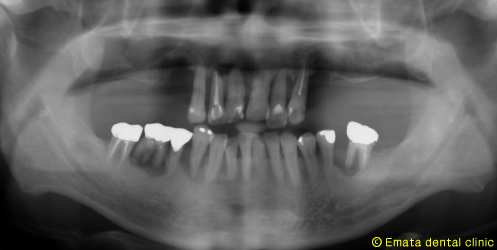

現在世界で最もインプラント治療を手がけているポルトガルのP.マロ先生よりAll-on-4(オールオンフォー)と呼ばれるコンセプトが提唱されました。

All-on-4(オールオンフォー)とは従来のインプラント治療に大きな変革をもたらす、画期的で最新の治療方法です。たった4本から6本でインプラントで12本分の歯を支えることを可能で手術が終わったとたんに入れ歯から開放され、固定式の歯がはいります。

では治療例をみてみましょう。

| All-on-4は4本ではないかとおもいますが、骨の状態や対合歯が自分の歯なのでより確実性をもたせたいため5本で立ち上げ、2本はスリープさせました。

この症例のポイントは、ソケットリフト部位への即時負荷でしょう。アダプテーションテクニックにより40ニュートンの初期固定がえられました(専門的になってしまいましたね)。 麻酔専門医の先生が静脈内鎮静法を行っていますので患者さんは半分寝ているうちに手術が終わってしまいます。 |